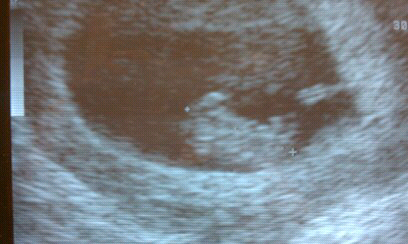

Our little peanut :)

I love this little baby already so much!

We were able to get an ultrasound before we left for Texas it was the best thing ever

We also saw the heartbeat its little legs moving back and forth.

I was suppose to be a little over 11 weeks.

They measured the little baby and moved back my due date two weeks..